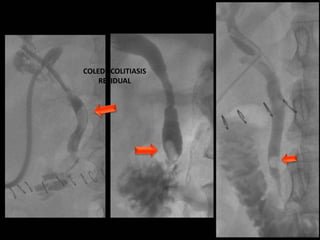

COLEDOCOLITIASIS

RESIDUAL

RESIDUAL CON DILATACIÓN

DE LA VIA BILIAR

• #19 Imagen por fluoroscopia evidencia imágenes radiopacas de bodes definidos en via biliar a nivel de colédoco A RELACIONAR CON COLEDOCOLITIASISS RESIDUAL